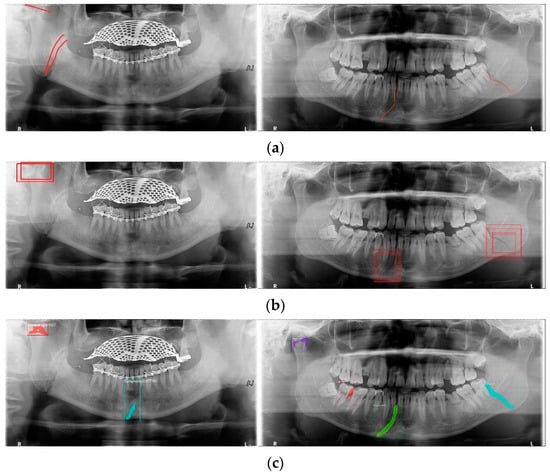

Figure 3.

The result of mandibular fracture detection: (a) diagnosis by oral and maxillofacial radiologist, (b) by LAT YOLOv4 module (with red boxes), (c) by Mask R-CNN (with colored polygons and boxes), and (d) by U-Net.

Unlike YOLO learning data consisting only of box coordinates and class information, Mask R-CNN requires the designation of a polygon-type learning region in the fracture region for the construction of a mandibular fracture learning dataset. However, in the case of shear fractures without gaps or dislocation fractures occurring in the condyle region, it was difficult to express the training data region using Mask R-CNN. Because these specific fracture regions cannot be drawn in closed polygon form, fracture regions are represented and trained in a box or simple form, such as YOLO learning data. In this case, for comparison with the results of the LAT YOLOv4 module [], training was performed with the same class structure on the same training data, and the detection results in the same test data were 57% precision, 70% recall, and 63% F1 scores. The fracture shape of the condyle region is not properly expressed, which leads to an error in judgment owing to the fracture shape, and the error detection between teeth is also recognized as a fracture in the panoramic image, resulting in a lower precision score (Figure 3c).

For U-Net training, a training dataset labeled according to the shape of the fracture is constructed. This makes it easy to generate U-Net training datasets of fracture sites with complex spacing. However, shear fractures or displaced fractures are difficult to be labeled. Therefore, in the case of shear fractures, the parts which are visible even with solid and crack lines in the shear fractures were labeled as much as possible. But the displaced fractures were not labeled because it adversely affected the fracture detection accuracy during U-Net training. Additionally, when segmentation and labeling are performed differently from complex fracture shapes, it adversely affects the training process and reduces mandibular fracture detection performance. Figure 3d confirms that U-Net shows good segmentation performance for general fracture types but U-Net shows poor segmentation performance for dislocated fractures in the condyle region because U-Net was not trained in condyle region. Therefore, U-Net is advantageous for learning the rest of the fracture areas except for some of the severe shear and displaced fractures.